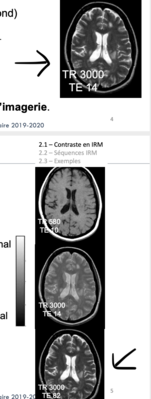

je ne comprends pas car les 2 coupes que je pointe semble être identique mais leur pondération est différente donc je ne comprends pas ce qui différencie une pondération en rho et en T2 sur cette coupe ou sur les autres..